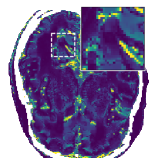

Figure 5 shows an example of a spatio-temporal regularization parameter-map which was estimated using the proposed approach for an acceleration factor of . The network estimates the regularization parameter-map to be pointwise relatively consistenly higher than the spatially required regularization. This result is in fact expected as the temporal dimension is the one for which the gradients of the images are the sparsest because of the high temporal correlation. Further, we see how the network consistently predicts both the spatial regularization as well as the temporal regularization to be less strong in the area where most of the movement is expected, i.e. in the cardiac region.

Figure 6 shows examples of the quantitative (magnitude) images of three of the 112 simulated inversion recovery measurements in the test dataset. We also show the regularization parameter-maps for regularization along the spatial directions and along the inversion-time direction generated by the network. The mean PSNR and SSIM of our proposed method is consistently higher for all considered acceleration factors, even compared to PDHG with regularization strength along spatial and inversion-time direction chosen by grid-search with access to the ground truth images (shown in Figure 8 and Table 2). The resulting parameter-maps after performing the regression on the reconstructed images are shown in Figure 7. Again, our proposed method results in the lowest RMS deviation from the ground truth images (Table 2).